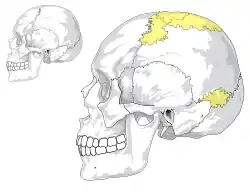

Wormian bones compared to a normal skull | |

Skull of a 21-year-old man with Wormian bones | |

Wormian bones, also known as intrasutural bones or sutural bones,[1] are extra bone pieces that can occur within a suture (joint) in the skull. These are irregular isolated bones that can appear in addition to the usual centres of ossification of the skull and, although unusual, are not rare.[2] They occur most frequently in the course of the lambdoid suture, which is more tortuous than other sutures. They are also occasionally seen within the sagittal and coronal sutures. A large wormian bone at lambda is often called an Inca bone (os incae),[3] due to the relatively high frequency of occurrence in Peruvian mummies. Another specific Wormian bone, the pterion ossicle, sometimes exists between the sphenoidal angle of the parietal bone and the great wing of the sphenoid bone.[4] They tend to vary in size and can be found on either side of the skull. Usually, not more than several are found in a single individual, but more than one hundred have been once found in the skull of a hydrocephalic adult.